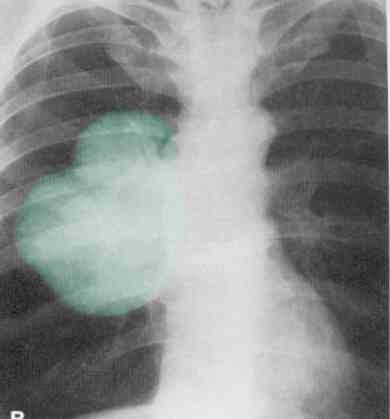

Typical radiation fields as per RTOG 0241